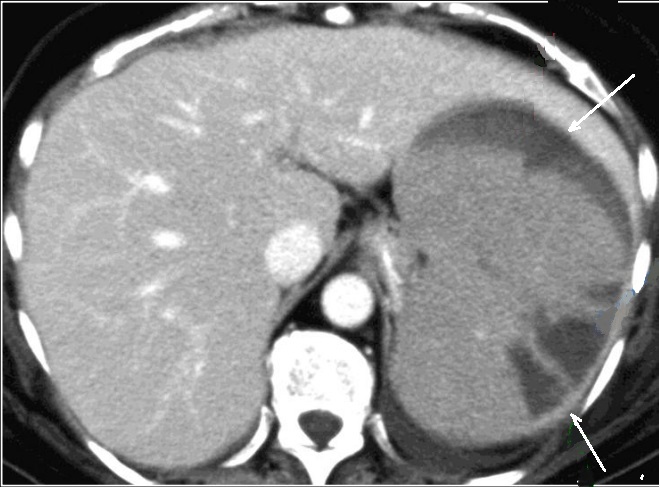

Aspect radiologique TDM d'une

traumatisme et contusion de la rate est image

hypodense lineaire ou en plage de mal limitees .

Image radiologique TDM d'une traumatisme de la rate

en coupe axiale et ẻn coup frontal |

|

Une autre traumatisme /

contusion de la rate est image hypodense en plage un

partie anterieure - interieure de la rate . Image radiologique

TDM en coupe axiale |